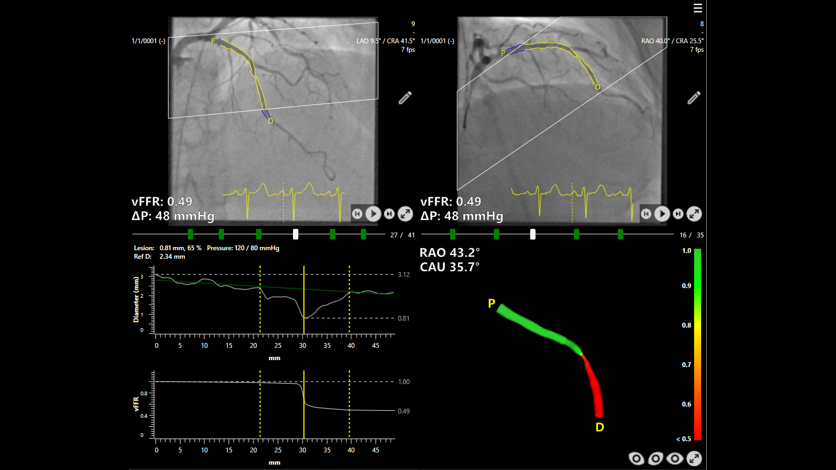

Today the results of the FAST III study, co-funded by Siemens Healthineers and Pie Medical Imaging, were presented at the Congress of the American College of Cardiology (ACC) and published in The New England Journal of Medicine (Angiography-Based Physiology to Guide Coronary Revascularization | New England Journal of Medicine). The results confirm the safety and efficacy of Caas vFFR – a software-based method developed by Pie Medical Imaging that calculates pressure drop and vessel fractional flow reserve from two angiographic images – as an alternative to conventional pressure wire-based physiology for guiding revascularization strategy in patients with intermediate coronary artery stenosis. This marks the end of the multicenter, randomized-controlled, open-label, non-inferiority study investigating the outcome of therapy for coronary artery disease after fractional flow reserve (FFR) has been determined using different methods. A total of 2,235 patients in 37 hospitals across seven European countries took part in the study, randomly selected for either the vFFR- or FFR-guided approach. FAST III marks the last important step in a ten-year evidence generation journey towards real-world outcome data.

Coronary stenoses are extremely common and clinically relevant as they sit at the center of coronary artery disease (CAD), the leading cause of death globally. FFR assesses how much coronary artery stenosis limits blood flow, with evidence showing that lesions causing less than a 20 percent flow reduction generally do not require treatment. Traditionally, FFR is measured by inserting a pressure wire into the coronary artery and inducing hyperemia with adenosine, a process that can cause the patients discomfort such as restlessness, chest pain, and shortness of breath. The FAST III study had evaluated whether percutaneous coronary intervention (PCI) guided by Caas vFFR can match the outcomes of the conventional invasive, pressure wire approach. This newer Caas vFFR technology offers a less invasive alternative by eliminating the need for both a pressure wire and hyperemic agents.

CAAS vFFR software by Pie Medical Imaging, as used in the FAST III study.